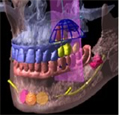

では、CTで撮影したものがどう見えるのかご覧下さい。

まだまだ、神経や血管の位置がよくわかりません。

神経、血管は大きいものが一本と言われていますが、実際は個人差があり、小さい血管神経も含めると、複数あると報告されています。

CTデータ3D立体構築画像変換検査の特徴について

実際にCTで撮影し、「CTデータ3D立体構築画像変換検査」したものがどう見えるのがご覧下さい。CTデータ3D立体構築画像変換検査した場合、3次元でどこにどのようにインプラントを埋め込んでいけばいいのか、立体的に把握することができます。

CTデータ3D立体構築画像変換検査は患者さまの顎の骨や歯の状況を立体的に把握します。あらゆる角度から検討でき、インプラントの植え込み位置、角度などの事前シミュレーションが的確に行われ、数値化することができます。

インプラント手術を行う前には、CTデータ3D立体構築画像変換検査で血管・神経の正確な位置の把握とばい菌の塊の位置などについても把握する必要があります。

この下記の写真は手術前に行う、3D立体画像構築画面です。

この患者さまの下顎の骨、そして神経が見えています。

この患者さまの下顎の骨、そして神経が見えています。

吉本歯科医院でインプラント治療を行う患者さまの顎の状態は、CT画像だけでなくここまで立体化されたものが手術前には手元にあり、シミュレーションを行ってから実際の手術に入るような流れをとっております。

さて、この写真、黄色くうにょうにょとしているのが神経です。

本来骨の厚みがある患者さまの場合は神経の黄色い部分は骨の中に隠れているため3D立体画像で真上から見た場合かくれて見えません。

この方の場合、骨が神経の出口(オトガイ孔)まで磨り減ったためにこのように写ります。